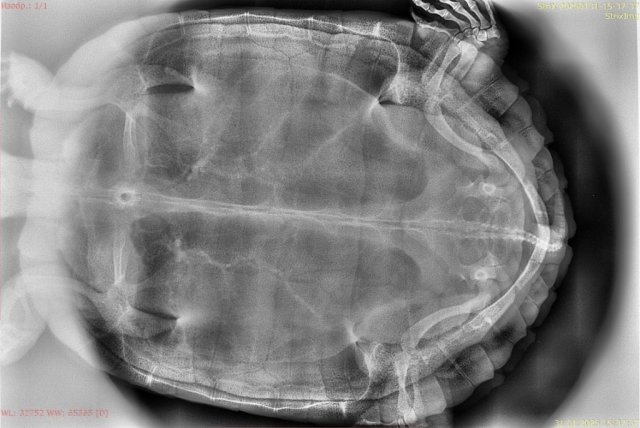

Татьяна.04 Ваше имя: Татьяна Локация: Россия, Люберцы Опубликовано: 31 января Автор Опубликовано: 31 января Сегодня сделали рентген. Всё чисто. Никаких патологий врач не обнаружил. Сказал, прогнать глистов